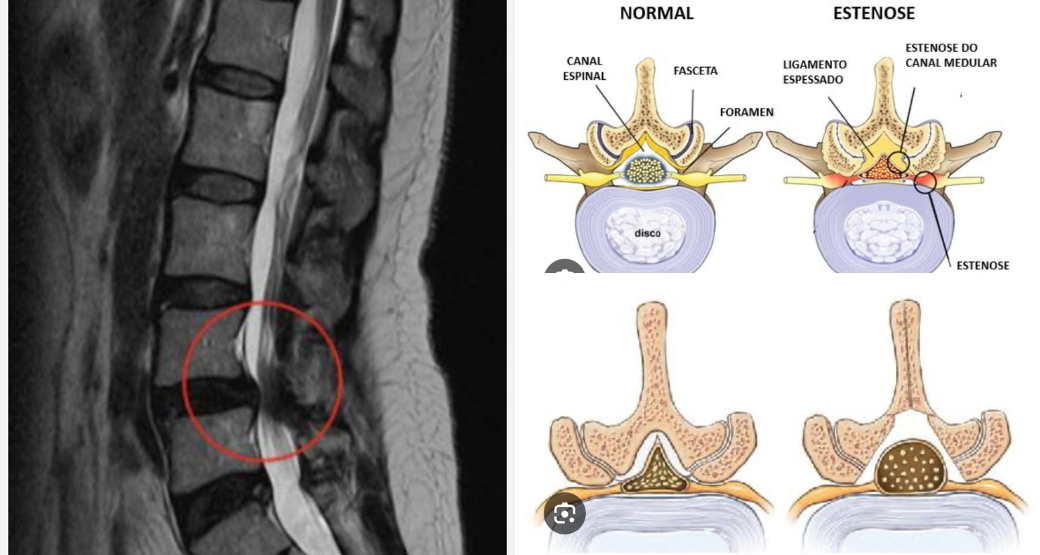

Descompressão endoscópica: Alívio para compressão radicular nas raízes L4 e L5?

“Sem dúvida... Realizamos com sucesso o procedimento em nosso paciente que sofria de dor lombar irradiada para membros inferiores e fraqueza muscular”, comemoram Edward Robert e Renato Bastos, cirurgiões ortopédicos.